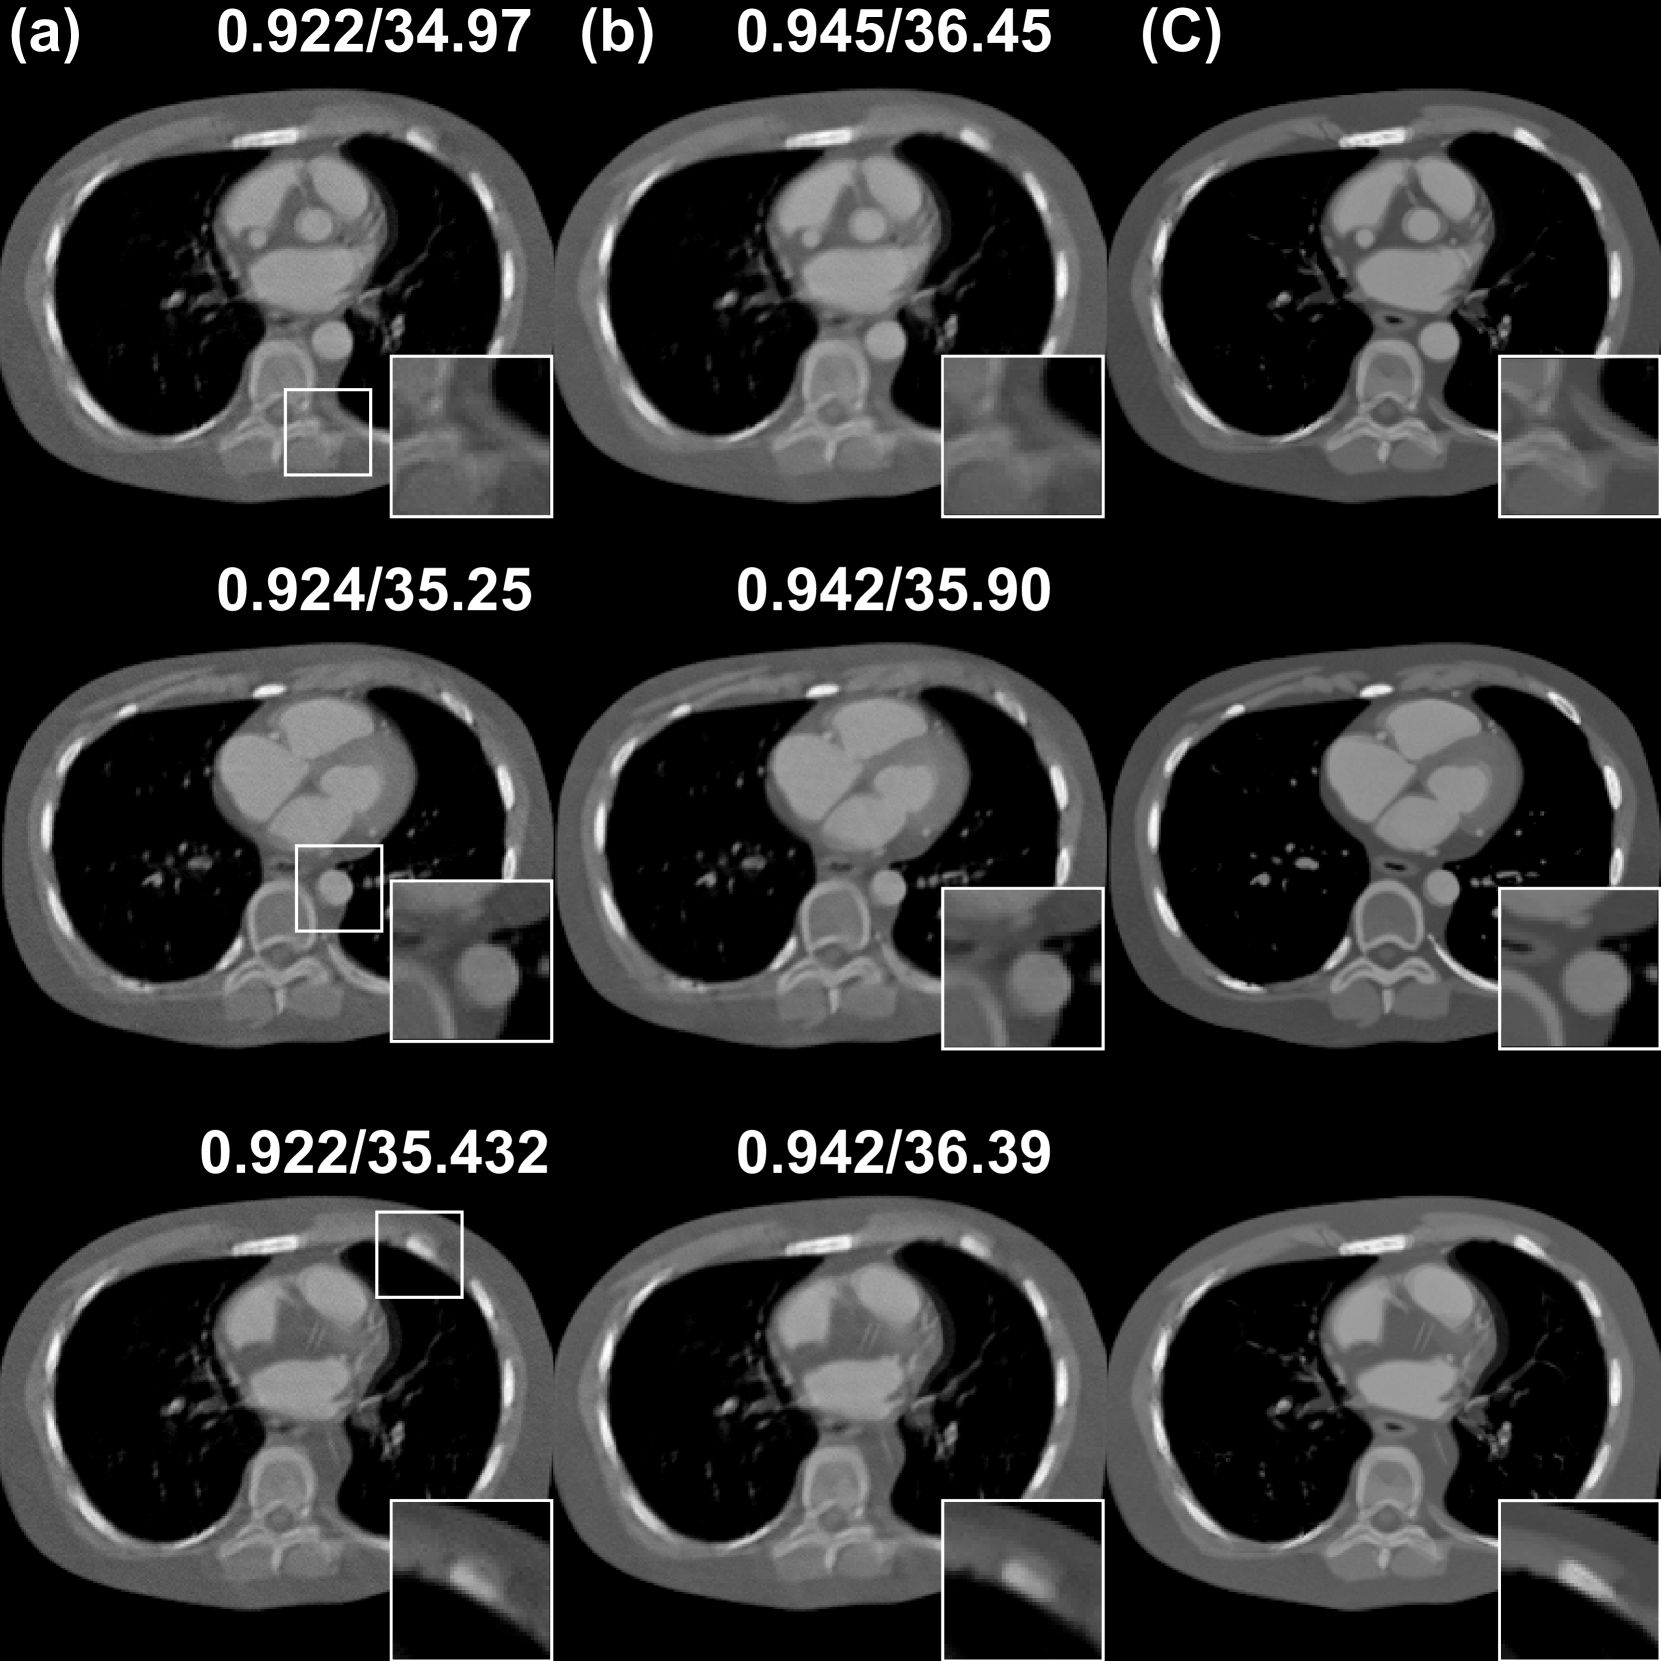

Refer to caption

Figure 7: Ablation study for the effect of TV term with 120 views using PSDM. (a) w/o TV prior, (b) w/ TV prior, (c) Ground truth. The display window is [540540-540- 540 1000100010001000] HU.

Figure 8: Reconstructed images of the PSDM and Diffusion-MBIR with respect to different reverse diffusion steps on 120 views. The display window is [540540-540- 540 1000100010001000] HU.

Figure. 7 presents a comparative analysis of the reconstruction results with and without the TV term. These quantitative metrics (SSIM and the PSNR) indicate that the TV term can improve the perceptual quality and the fidelity of the reconstructed images. Visually, results with the TV term exhibit less noise and more consistent structural integrity compared to those without the TV prior. Figure. 8 illustrates the performance comparison between PSDM and Diffusion-MBIR with respect to numbers of reverse diffusion steps. It is observed that PSDM demonstrates faster convergence relative to Diffusion-MBIR. Specifically, in the iterations ranging from 600 to 800, Diffusion-MBIR exhibits higher noise levels compared to PSDM. Figure 9 provides a quantitative comparison of the performance with and without the Fourier fusion module. It is observed that between 400-800 reverse steps, the PSDM (presumably a metric being compared) with the Fourier fusion module outperforms the one without it. Ultimately, both the PSNR and SSIM metrics show a slight improvement when the Fourier fusion module is utilized, highlighting its benefits.